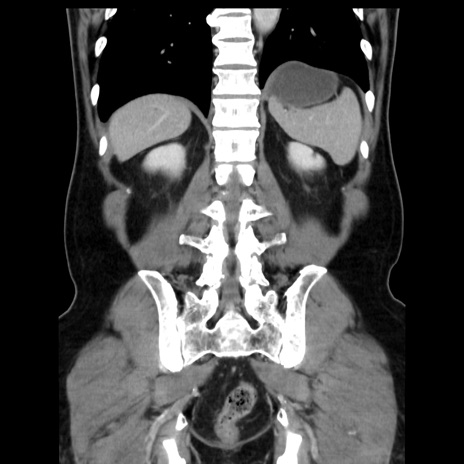

症例16(冠状断像)

【症例】 70歳代男性

【主訴】 腹痛、嘔吐

【現病歴】 約1ヶ月前より間欠的に腹痛と嘔吐あり、当院消化器内科を受診したところCTで多発する肝臓のLDAを指摘され、精査中であった。以降は消化器症状は安定していたが、2日前より嘔気と腹痛があり、同日より排便・排ガスが消失した。改善認めず、 本日、救急外来を受診した。

【既往歴】 大腸ポリープ切除後。

【身体所見】意識清明・会話良好、BT 36.3℃、BP 127/80mmHg、 P 80bpm、腹部:膨満あり、平坦・軟、上腹部正中および下腹部正中に圧痛あり、反跳痛なし、筋性防御なし。

【データ】WBC 7200、CRP 0.77